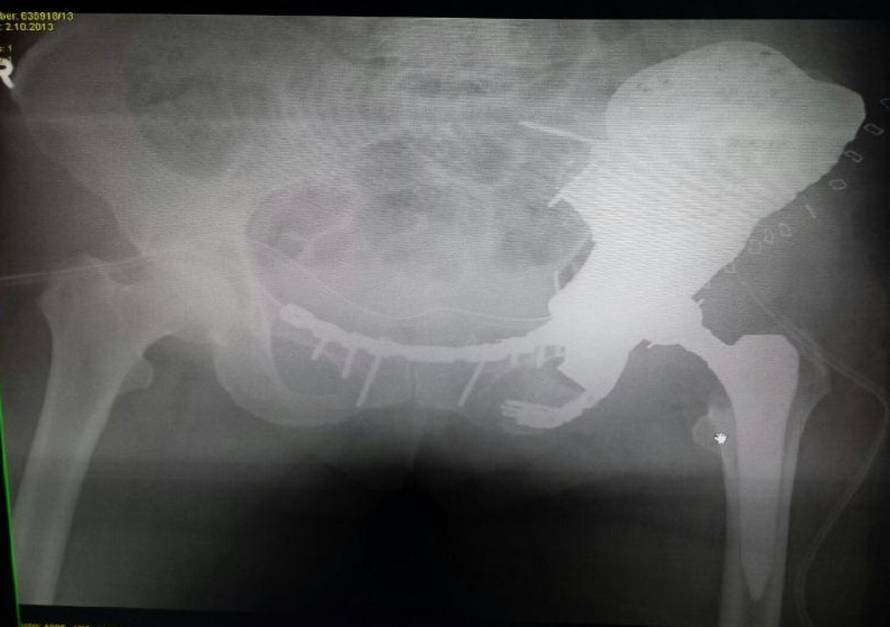

Liječnici iz KBC Sestre milosrdnice u Engleskoj su isprintali dio zdjelice i ugradili ga Dubrovčanki (66). Revolucionarni zahvat u Hrvatskoj, i regiji, dosad nije izveden